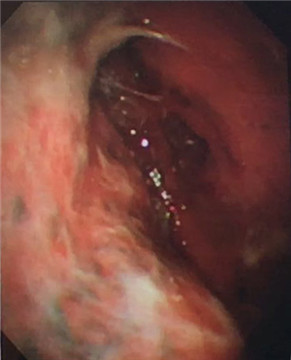

多發(fā)黃白色小結(jié)節(jié)

7月21日建立人工氣胸,擴(kuò)張肺部。7月22日,由周傳毅主任、張健主治醫(yī)師共同實(shí)施了胸腔鏡檢查,并活檢取出多處胸膜小結(jié)節(jié)。術(shù)后經(jīng)病理診斷,確診為結(jié)核性胸膜炎。檢查過程無任何不適,后續(xù)配合抗結(jié)核藥物治療,王爺爺恢復(fù)良好,已出院返家。

我院呼吸內(nèi)科采用改良型“軟式胸腔鏡”,該新設(shè)備軟硬結(jié)合,前端可彎曲,能多方向觀察胸腔內(nèi)改變,比老式“硬式胸腔鏡”的探查視野更大,診斷更準(zhǔn)確。